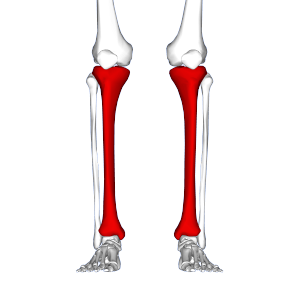

Red area represents tibia. MTSS pain found on inner and lower 2/3rds of tibia. | |

Shin splints, also known as medial tibial stress syndrome (MTSS), is defined by the American Academy of Orthopaedic Surgeons as "pain along the inner edge of the shinbone (tibia)."[1] Shin splints are usually caused by repeated trauma to the connective muscle tissue surrounding the tibia. They are a common injury affecting athletes who engage in running sports or other forms of physical activity, including running and jumping. They are characterized by general pain in the lower region of the leg between the knee and the ankle. Shin splints injuries are specifically located in the middle to lower thirds of the outside or lateral part of the tibia, which is the larger of two bones comprising the lower leg.

Shin splint pain is described as a recurring dull ache along the inner part of the lower two-thirds of the tibia.[9] In contrast, stress fracture pain is localized to the fracture site.[10]